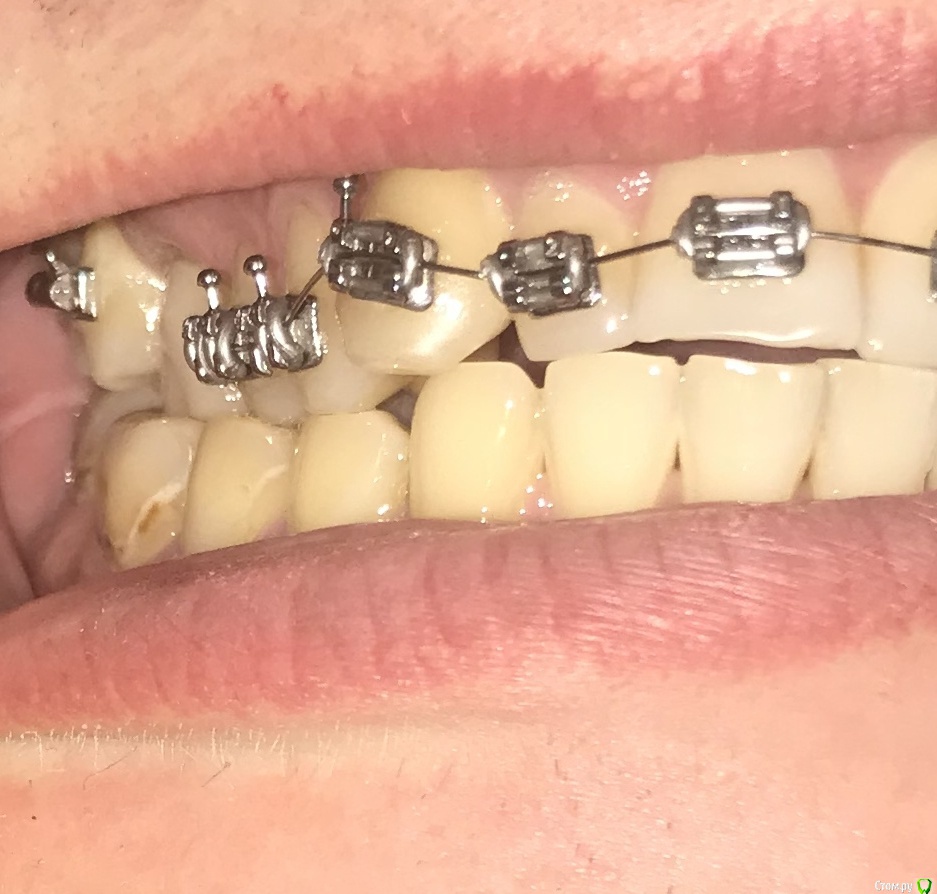

Ситуация такая, что начал лечение у ортодонта, но как оказалось, сильно исправлять прикус он не будет, только выравнивание зубного ряда. Расстояние выноса верхних зубов вперед в ширину четверки, но удалять четверки мне бы не хотелось. Так же, есть смещение в бок. Есть одна коронка и одна вкладка, много зубных каналов запломбировано. В целом, сильных проблем с прикусом я не ощущаю, но не будет ли потом проблем с челюстным суставом? Морально я готов к лечению, хотелось бы все сделать раз и навсегда, но с чего начать, какими способами нужно будет все исправлять? Придется ли делать операцию на челюсти или как то выносить нижнюю челюсть вперед другими способами? Нужно ли удалять восьмерки(осталась пара)?

И самое главное, необходимо найти грамотного специалиста и клинику, очень не хотелось бы иметь какие то проблемы со здоровьем после всех изменений, а так же бесконечного перелечивания, как у некоторых. Мне 31. Буду благодарен, если кто посоветует врача, желательно по собственному опыту или по хорошим отзывам в городе Москва, южная часть Подмосковья.